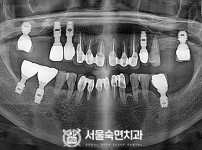

임플란트-전후사진1

치과를-선택할-때-꼭-확인하세요-서울숙면치과-임플란트-전후사진